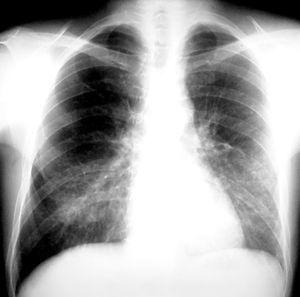

Dentro de las pruebas no invasivas, la tomografía computarizada de alta resolución (TCAR) se ha convertido en un elemento indispensable para establecer un diagnóstico precoz de IFI42-44. Ésta presenta una cinética característica a lo largo del proceso. En el momento del diagnóstico, fase precoz de la infección, el "signo del halo" es el hallazgo más frecuente y se corresponde con una zona de edema o hemorragia de baja atenuación alrededor de una masa o nódulo (figs. 2 y 3). Más adelante, las lesiones se cavitan, aparece aire en su interior y toman aspecto de semiluna42,43.

Figura 2. Signo del halo en aspergilosis invasora.